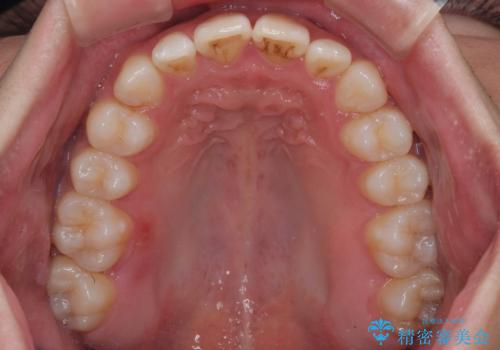

- 治療期間

- 1年2ヶ月

- 治療回数

- 10-30回